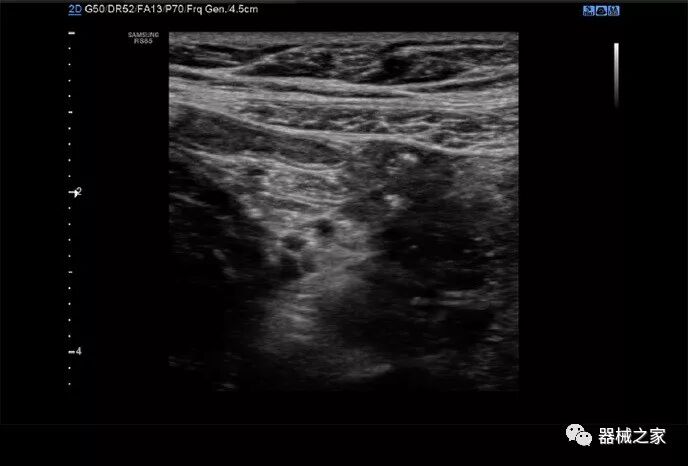

三星RS85超声系统于2018年获得FDA批准,其设计目的是将许多多步骤操作组合成一个步骤,以减少击键和重复的用户交互。

在几年前,超声波无法对小型慢流血管中的血流进行成像,但现在有少数供应商提供具有此功能的系统。该特征提供了另外一种检查病变以指示癌症或炎症的方法。其中一个是佳能Aplio 900 CV系统,它可以显示毛细血管中的血流量。日立的Arietta 65中程系统提供了一种可视化小血管的功能,可以更好地观察肾脏等器官的灌注情况。三星RS85还提供MV-Flow可视化慢流微血管结构。